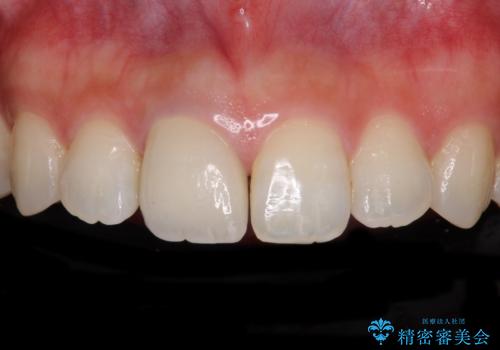

- 近医にて被せた前歯のクラウンの色の違いを気にして来院された患者様です。

オーダーメイドのオールセラミッククラウンにて補綴することとしました。

元々すきっ歯であったため、隙間を全て埋めると左右で大きさがアンバランスとなることが懸念されました。

違和感のない程度に隙間を小さくして、自然な見た目に仕上げました。